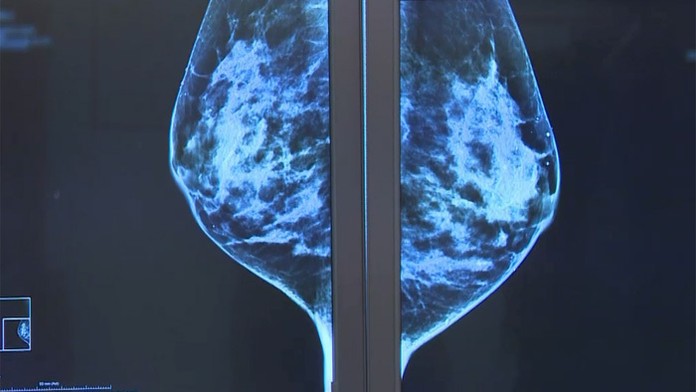

Karcinóm prsníka má stále viac a viac žien. Potvrdzuje to Svetová zdravotnícka organizácia, ale aj lekári na Slovensku.

Rakovina prsníka zostáva naďalej obrovským strašiakom žien. Lekári celosvetovo zaznamenávajú čoraz vyšší výskyt tohto zákerného ochorenia. Za jeho nárastom je starnutie populácie, ale aj zanedbaná prevencia. Vo svete ročne zomrie na rakovinu prsníka asi pol milióna žien.

Lekári však chvália uvedomelosť Sloveniek. Väčšina z nás prevenciu nezanedbáva. Tou najjednoduchšou zostáva samovyšetrenie prsníkov. V ambulanciách pre zmenu absolvujeme sono alebo mamografiu. Stále sa však vyskytujú prípady, keď s nádorom prídeme k lekárovi neskoro.